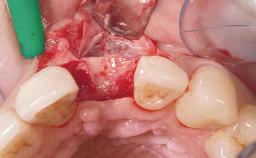

A 42-year-old female patient was referred to our clinic at the School of Dentistry of the University of São Paulo in November 2004, presenting a deficient restoration in the upper left central incisor. The clinical examination revealed no gingival retraction or any signs of gingival inflammation and, therefore, previous periodontal treatment was not considered. The patient presented a high lip line at full smile and a thin tissue biotype. This combination characterized a high-risk situation from an anatomic point of view, which required careful preoperative planning and cautious surgical execution.

Lip Line No exposure of papillae Exposure of papillae Full exposure of mucosa margin

Periodontal Phenotype Low-scalloped, thick Medium-scalloped, medium-thick High-scalloped, thin

Soft Tissue Anatomy Intact Defective

Loading Protocol Immediate

Provisional Implant-Supported Prosthesis Prosthodontic margin < 3 mm apical to mucosal margin Prosthodontic margin < 3 mm apical to mucosal margin